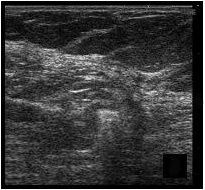

Se prepara la piel con anestesia local (lidocaína 1%) y para la punción ecodirigida del radiotrazador se utiliza una aguja espinal de calibre de 22 G. El radiotrazador nos lo aporta el Servicio de Medicina Nuclear y se trata del 99mtecnecio-coloide de albúmina (Nanocoll®, Amershan Health). La dosis es de 0,8-2 mCi diluidos en suero salino, lo que supone un volumen a inyectar de entre 0,3 a 1 ml. El radiotrazador se inyecta con control ecográfico en la periferia de la lesión con lo que, no sólo se localiza ésta, sino que se permite la migración del mismo hasta el ganglio centinela. Durante la inyección se comprueba cómo se produce un cambio de la ecogenicidad en el extremo de la aguja (fig. 1).

Fig. 1.--Nódulo hipoecoico visible en la ecografía (A). Durante la inyección del radiotrazador se produce un cambio de la ecogenicidad en el extremo de la aguja (B).